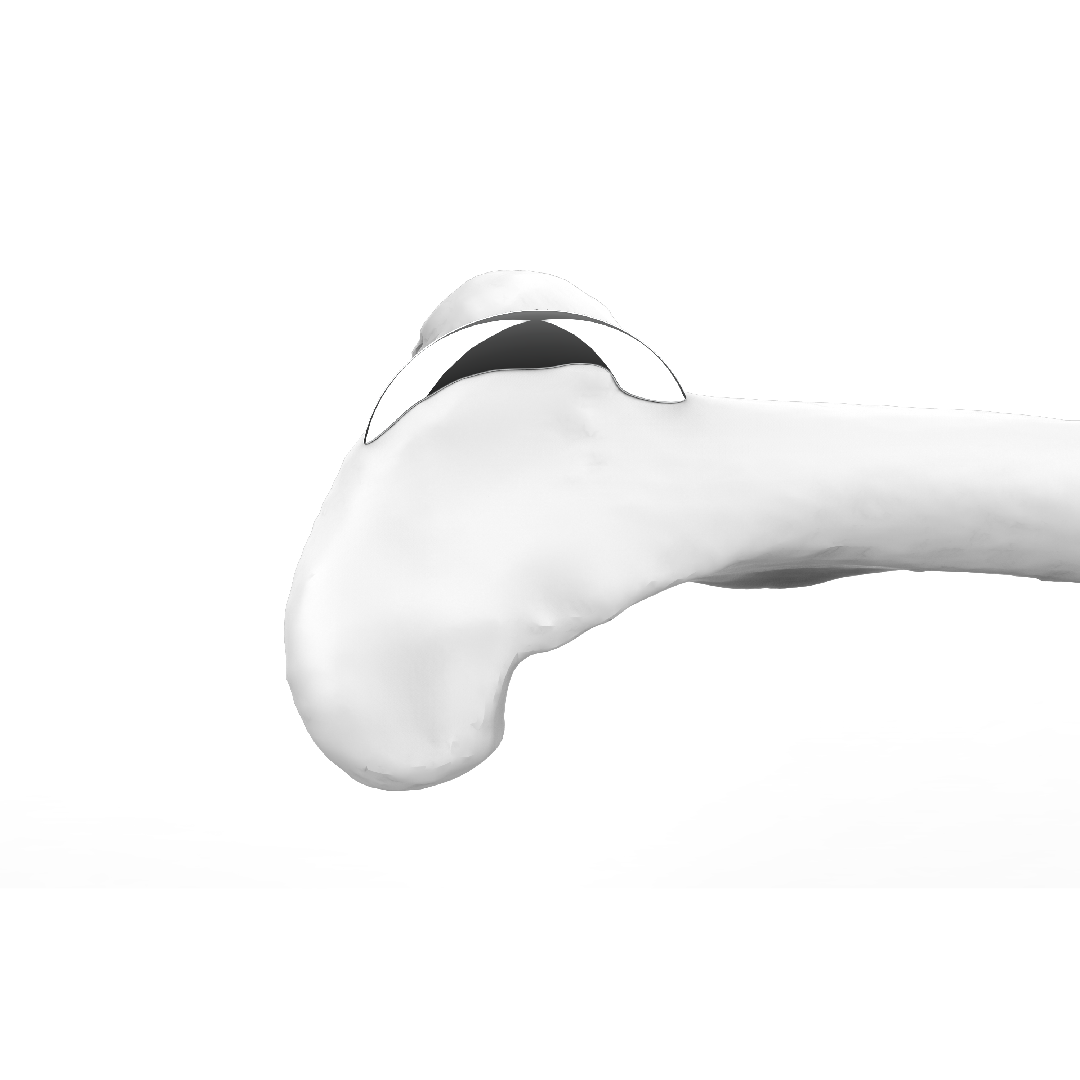

Trochlear Ridge Prostheses (TRP)

TRP è stata progettata per offrire ai chirurghi veterinari un ulteriore strumento nel trattamento della lussazione della rotula.

TRP è un impianto protesico personalizzato che permette di rialzare, secondo necessità, i bordi trocleari del femore, migliorando così il contenimento della rotula nella sua sede anatomica non alterando l’anatomia del paziente.

TRP rappresenta un’alternativa all’intervento di solcoplastica, con l’obiettivo di ridurre al minimo l’invasività della procedura per il paziente e di ridurre i tempi chirurgici.

La personalizzazione della protesi, disegnata sulla base della ricostruzione tridimensionale dell’osso del paziente, consente all’impianto di adattarsi all’osso e non viceversa. La sua applicazione non prevede le ostectomie necessarie nella pratica chirurgica con impianti standardizzati.